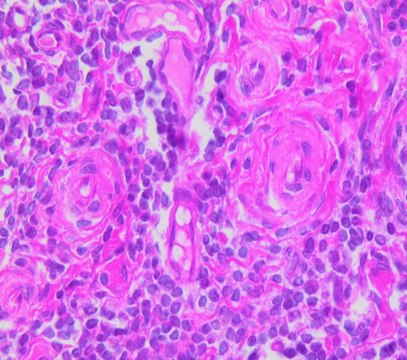

hematology

histology